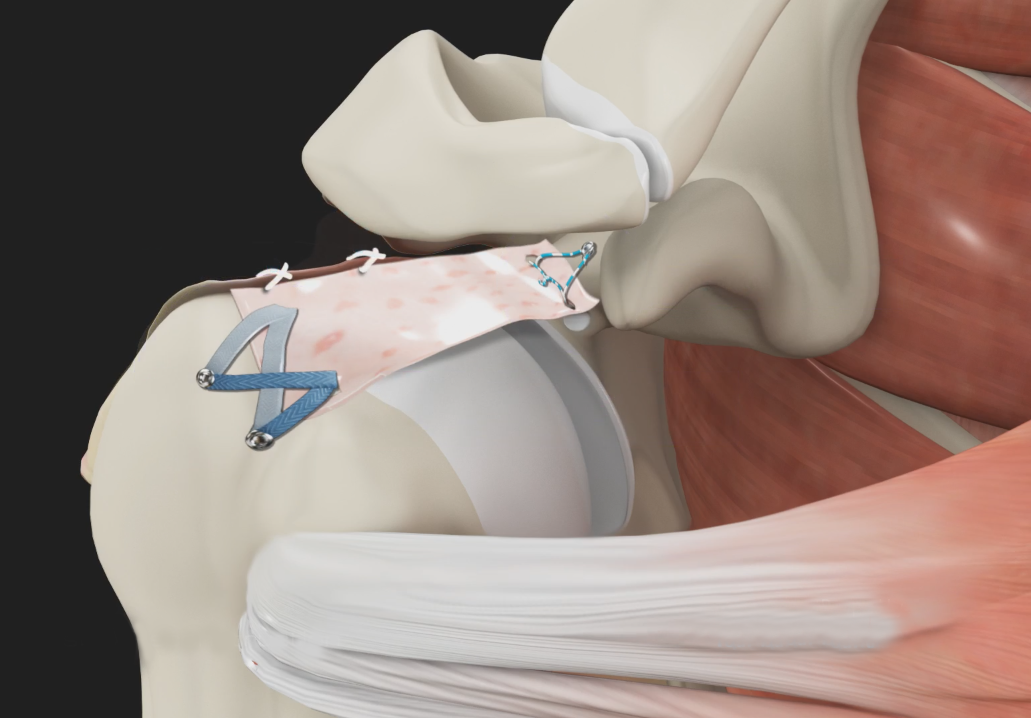

Rotator Cuff Repair

The rotator cuff is a group of 4 muscles in the shoulder joint including the supraspinatus, infraspinatus, teres minor, and subscapularis.

Revision Rotator Cuff Surgery

Revision rotator cuff surgery is a procedure done to repair a re-tear in the rotator cuff after a failed initial rotator cuff surgery.